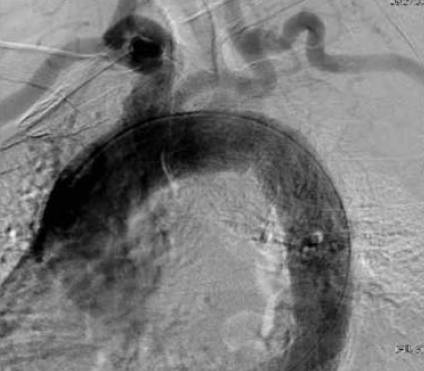

2. ábra.

PAU az aorta ascendensen.

Az aorta ascendensen lévő PAU esetében az ascendens pótlását nyitott aorto-aorticus interpositioval oldottuk meg (2. ábra). Az aortaív hybrid műtéteinél az aortaív görbületét jól követő Gore Tag® graftot alkalmaztunk. 2 esetben a proximalis rögzítési zóna az aorta ascendens (landing zone 0), 2 esetben az anonyma és a bal carotis communis között (landing zone I) és 4 további betegnél a bal a. carotis communis és bal a. subclavia között (landing zone II) volt. Egy esetben a bal a. subclavia szájadékát transpositio nélkül lefedtük, amit a jó jobb oldali vertebralis keringés tett lehetővé. A postoperatív szakban a bal karon funkcionális panaszok nem jelentkeztek. A thoracalis aortán a proximalis rögzítési (landing) zónákat 4. Táblázatunk mutatja. Az aorta descendens álaneurysmáit transfemoralisan [6] illeve az a. iliaca communison [1] át felvezetett Medtronic Valiant Captivia® endografttal fedtük le. A distalis aorta descendens, thoracoabdominalis szakaszán egy esetben folt plasticát, egyben inlay interpositiot végeztünk nyitott beavatkozásként. Műtéti megoldásainkat a 2. Táblázatunkon foglaltuk össze.